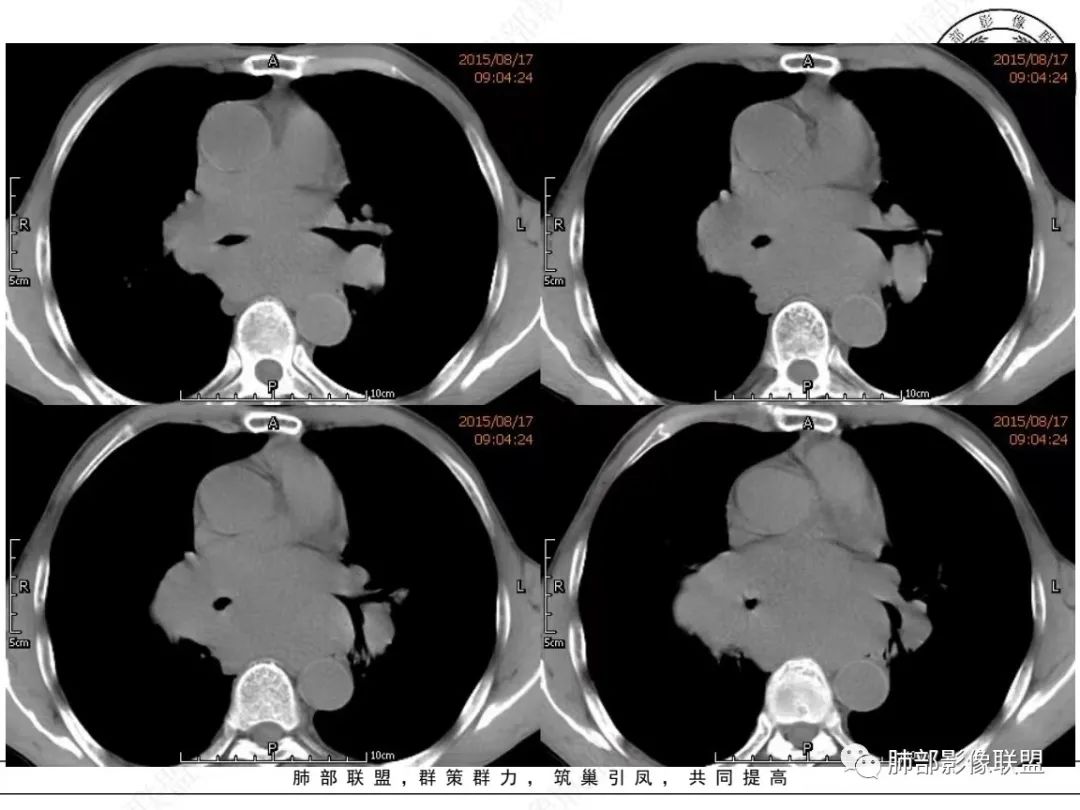

放射小白:老年男性,右侧肺门可见团块状占位包绕气管,气管受压变窄,纵隔见巨大团块状占位,另纵隔可见肿大淋巴结,增强肺门及纵隔肿块强化不明显,内部可见血管影,周围结构只是受压移位,另颌下淋巴结穿刺慢性淋巴结炎,首先考虑小细胞癌,鉴别淋巴瘤、结节病。

宇宙:右肺下叶小结节,右肺门及中后纵膈淋巴结肿大融合,强化均匀,主支气管、中间段及下叶支气管受压变窄,右下肺静脉受压变窄,考虑小细胞癌,鉴别淋巴瘤

丽:老年男性,纵隔及肺门多发肿大淋巴结,相互融合呈团块状,包绕支气管官腔,呈针尖样狭窄,增强后轻度强化,考虑小细胞肺癌

放射线:纵隔及肺门淋巴结肿大相互融合呈冰冻纵膈,支气管受压变窄呈针孔样,老年男性吸烟患者,考虑小细胞肺癌。

采莲:老年男性,有吸烟史,双颈部肿块,双肺纵隔淋巴结多发淋巴结肿大并融合成块,气管及右肺下叶支气管受压狭窄,考虑恶性,淋巴瘤可能,鉴别小细胞肺癌。

崔少钢:老年男性,有吸烟史,右肺下叶背段示小结节,纵隔、腋窝及右肺门淋巴结节肿大,气管受压狭窄,后纵隔软组织内示血管走行,考虑小细胞>淋巴瘤。

我只是邓较瘦:晨读老年男性,长期吸烟。右肺门、纵隔多发肿大淋巴结、融合成团块,中间支气管、右肺下叶支气管受压变窄,增强扫描强化程度较轻,血管包埋。另两侧腋窝亦见多发肿大淋巴结。常规恶性没问题,小细胞?淋巴瘤?但是於老师的病例总感觉没那么简单。

谢加平:纵隔内中后纵隔及右肺门淋巴结肿大,形成大肿块,整体密度均匀,并轻度强化,见“血管飘浮”征,包绕气管分叉及右主支气管及中间段支气管明显受压狭窄,并包埋右肺门血管束,无侵蚀破坏,右肺动脉后壁见压迹影,右肺下叶背段有阻塞性炎症,首选淋巴瘤,支气管超声内镜活检,明确诊断!